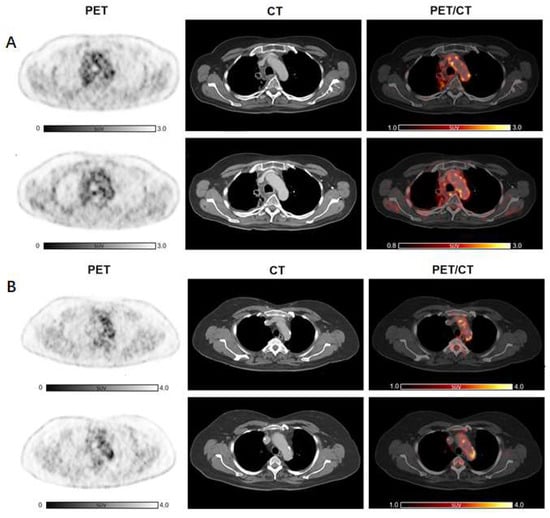

Figure 4. Increased 2-[18F]FDG arterial uptake after ICI therapy compared to baseline in a subject without any other previous anti-cancer treatment. Cancer immunotherapy with ICI resulted in a modest but significant increase in arterial 2-[18F]FDG in a patient not previously treated with other anti-cancer therapies, such as CHT or RT. Abbreviations: CHT, chemotherapy; 2-[18F]FDG, 2-[18F]fluoro-d-glucose; ICI, immune checkpoint inhibitors; RT, radiotherapy.

Subsequently, we analyzed the change in arterial inflammatory activity by dividing the patients into two groups, according to the presence of previous anti-cancer treatments, such as CHT or RT, and with presence/absence of CVD risk factors. Cancer immunotherapy with ICI resulted in a significant increase in inflammatory activity in patients without previous CHT (n = 19, TBRCHT(−)_pre = 1.64 ± 0.26 vs. TBRCHT(−)_post = 1.91 ± 0.36; p < 0.001). In patients treated previously with CHT, TBRs remained substantially unchanged (n = 28, TBRCHT(+)_pre = 1.79 ± 0.25 vs. TBRCHT(+)_post = 1.88 ± 0.34; p = 0.18) (Figure 2B). Furthermore, significantly elevated TBR values were recorded after therapy in the subjects without previous RT (n = 25, TBRRT(−)_pre = 1.68 ± 0.25 vs. TBRRT(-)_post = 1.93 ± 0.38; p < 0.001), while no significant changes were observed in patients with prior RT (n = 22, TBRRT(+) _pre = 1.78 ± 0.26 vs. TBRRT(+)_post = 1.84 ± 0.29; p = 0.34) (Figure 2B). Representative images are shown in Figure 3 as well as in Figure 4.